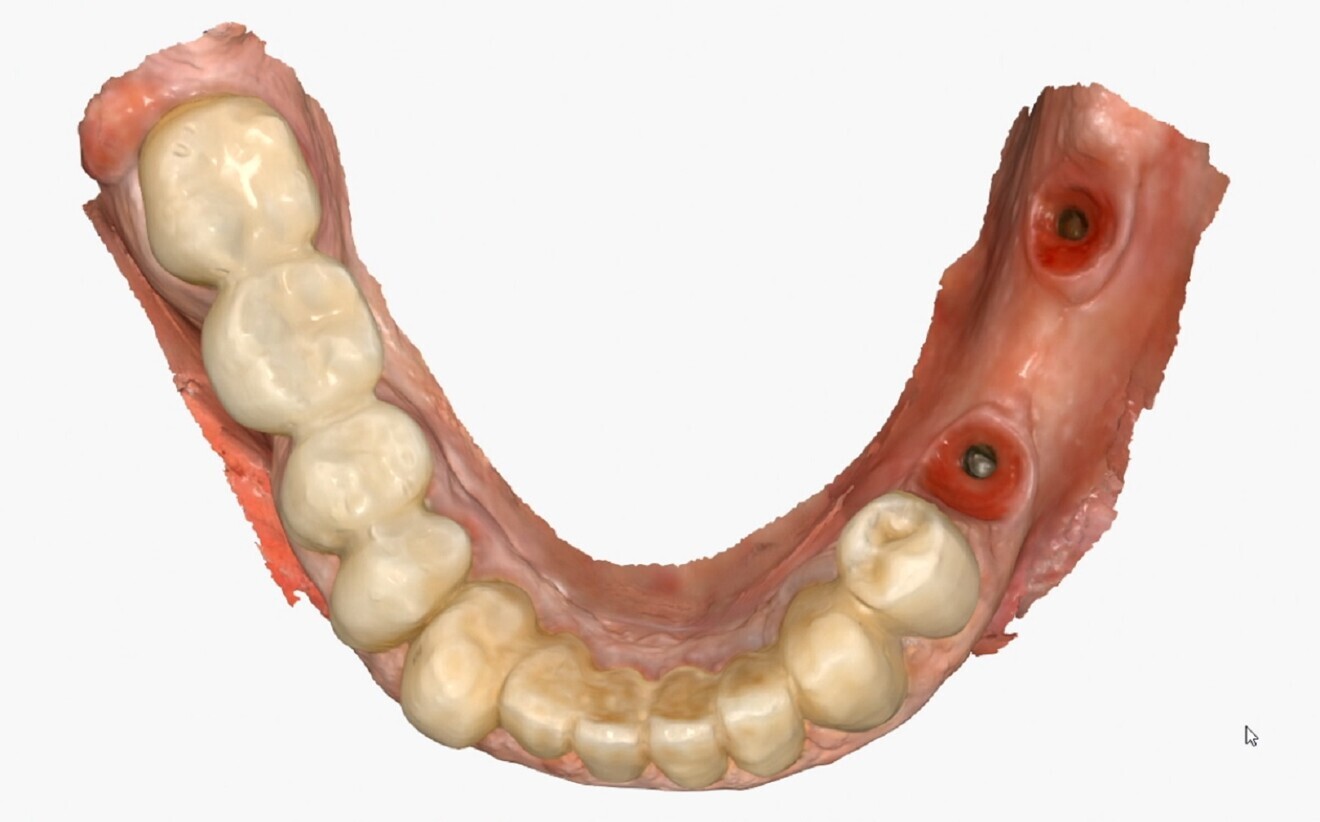

Intra-oral scanning After postoperative healing of the implants, multi-unit abutments and ProCam scan bodies were placed over the implants, and data was acquired with the Medit i700 wireless intra-oral scanner (Figs. 2a & b). The use of the intra-oral scanner allowed us to avoid physical impressions, thereby reducing patient discomfort. It also allowed for the capture of a detailed and accurate digital representation of the implant connections and enabled real-time evaluation of the scan quality.

The use of intra-oral scanners to capture impressions has demonstrated high accuracy compared with conventional techniques.1, 2 The importance of ensuring a precise intra-oral scan is often under-estimated, and accurate intra-oral data capture is the true starting point for a successful restoration. Accurate transfer of the implant position is essential for achieving a perfect match between the digital design and clinical reality. Having an optimised geometry and being made of a highly readable scanning material, the ProCam scan bodies allowed the position of the implants and the profile of the peri-implant tissue to be captured with extreme fidelity (Fig. 3).

Figs. 2a & b:: Intra-oral scanning using ProCam scan bodies.

Fig. 2b

Fig. 3: Extreme fidelity of capture of the implant position and surrounding tissue profile using the ProCam scan bodies.